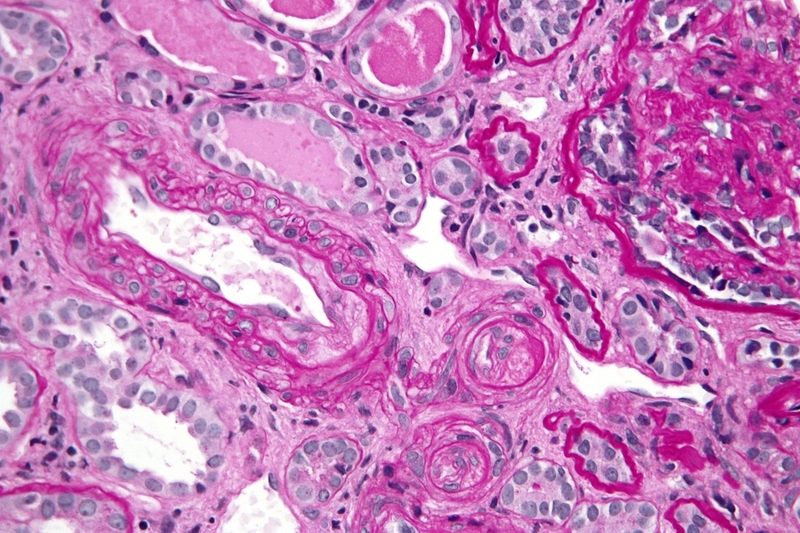

Hội chứng kháng thể kháng Phospholipid (Antiphospholipid antibodies syndrome - APS) thuộc nhóm bệnh tự miễn. Khi mắc phải hội chứng này, các kháng thể của hệ miễn dịch nhầm lẫn chất béo có trong tế bào Phospholipid thành chất có hại và tấn công. Các tế bào đó sẽ bị tổn thương. Những tổn thương này gây hình thành các khối máu đông ở động mạch và tĩnh mạch.

APS là hội chứng rối loạn làm tăng nguy cơ đông máuTình trạng đông máu là hiện tượng bình thường trong cơ thể giúp vết thương nhỏ hoặc thành mạch máu bị vỡ nhanh lành hơn. Tuy nhiên, khi mắc phải hội chứng kháng thể kháng phospholipid, máu đông quá mức gây tắc dòng chảy của máu dẫn đến tổn hại các bộ phận trong cơ thể.